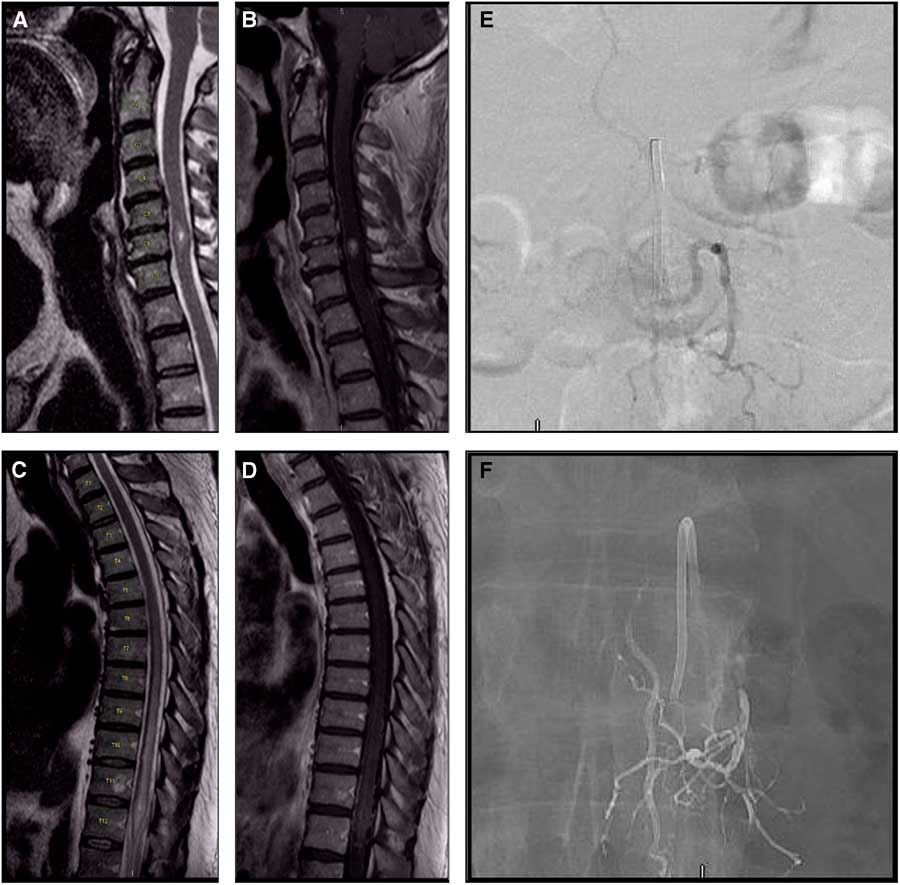

Neuroimaging showed an enhancing C6 intramedullary lesion and diffuse T2 signal abnormality in the thoracic cord (extending from T5-T6 through the conus medullaris) as well as vascular flow voids along the dorsal surface of the lower cord to the conus medullaris (Figure 1A-1D). Cerebrospinal fluid examination was unremarkable. He received a 5-day course of IV steroids, with minimal symptomatic improvement. Further investigation with spinal angiography revealed a L1 dural arteriovenous fistula (dAVF) (Figure 1E). The dAVF was subsequently embolized with significant clinical improvement (Figure 1F). The cervical lesion was observed with periodic surveillance. Three-month follow-up spinal/cerebral angiography showed no residual vascular lesion or evidence of any vascular malformation in the cervical topography. Six-month follow-up imaging showed that the intramedullary cervical lesion had remained stable.

Figure 1 Spinal MRI: sagittal T2 (A) and postcontrast sagittal T1 (B) show an enhancing C6 9 mm intramedullary lesion with mild expansion of the cord and focal edema; (C) sagittal T2 and postcontrast sagittal T1 (D) show diffuse signal abnormality from T5-T6 to the conus medullaris and vascular flow voids along the dorsal surface of the lower cord to the conus medullaris. Spinal angiography (E,F). Pre-embolization spinal angiography (E): anteroposterior injection of the left L1 segmental artery shows a type 1 dural arteriovenous fistula; note arterialized vein at midline. Post-embolization spinal angiography (F) shows Onyx in the left L1 segmental artery (previous point of fistularization) and complete obliteration of the arterialized vein without residual shunting.